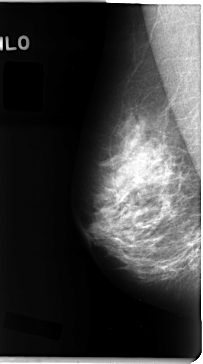

C_0097_1.LEFT_MLO

LEFT_MLO LINES 4672 PIXELS_PER_LINE 2616 BITS_PER_PIXEL 12 RESOLUTION 50 OVERLAY